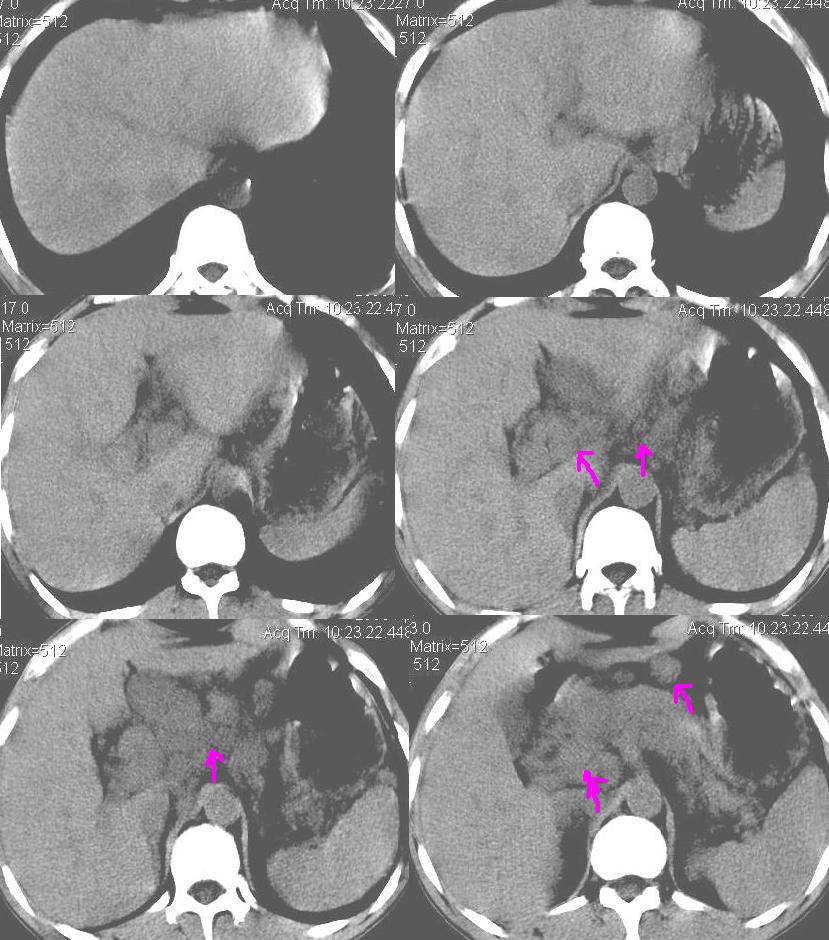

上腹部疼痛一月,呕吐10天,发现左侧颈部包快10天 胸部cr片未见明显异常。

腹膜后淋巴结增大,转移、淋巴瘤?胰腺增大,胰腺炎?占位?颈部考虑增大淋巴结。建议腹部增强扫描。

连最基本的ct值都没有测        腹部的窗宽窗位太大了     影响诊断

黑!广泛淋巴结肿大不符合胰腺癌转移。胰腺周围淋巴结肿大致使胰腺看起来大。考虑淋巴瘤可能大。

图像黑了点!